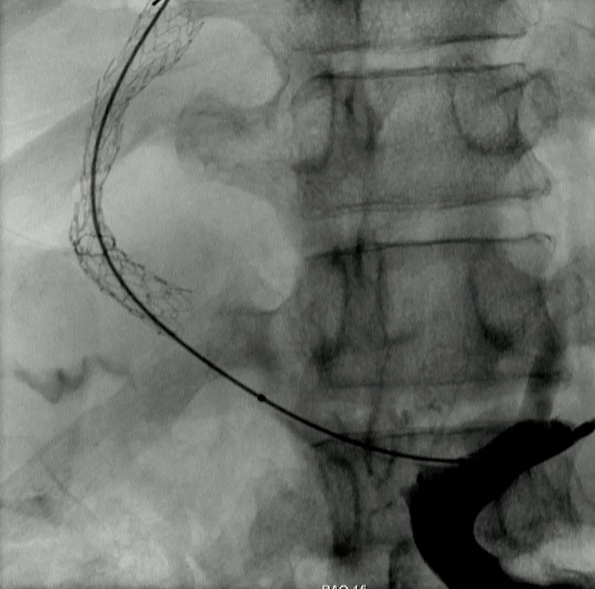

该程序包含以下步骤: 经脾脏入路:在超声引导下,刺穿脾静脉内的一个实质内分支。 在通过脾静脉造影确认了静脉通路后,导管和导丝被推进,以穿过脾静脉并抵达血栓化的门静脉。在门静脉/右门静脉分支处放置圈套器,为TIPS穿刺精准定位。TIPS穿刺圈套器,并穿过圈套器完成TIPS

步骤: 鉴于慢性血栓形成的复杂性: 一种经脾脏途径的门静脉再通术(PVR)。 随后是经颈静脉肝内门体分流术 。

结果:术后影像学检查显示门静脉和脾静脉的血流情况有所改善,且残留血栓极少。